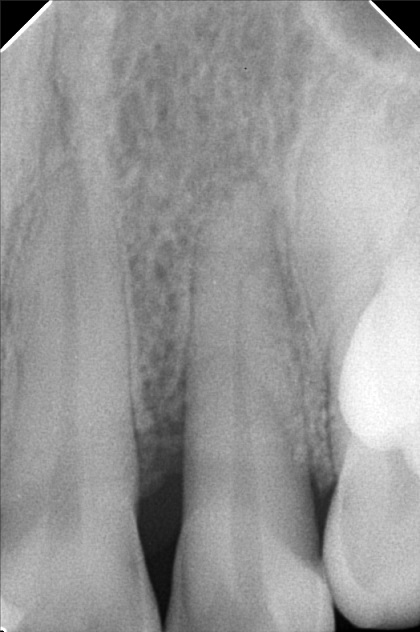

- Procedure

- ilumin_abegail.jpg